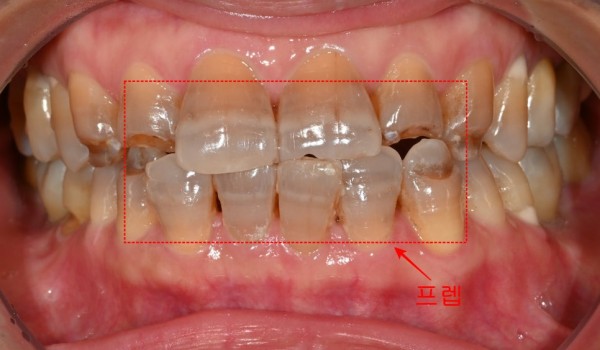

이번에 소개해드릴 사례는 테트라사이클린 항생제 복용으로 인한

치아 변색으로 고생하셨던 환자분의 치료 과정입니다.

복용했던 항생제로 인해 전체적으로 치아들이

회색빛을 띠게 되어 계속 고민이 되셨던 케이스였습니다.

초진 검사에서 사진에서 보시는 것과 같이 치아에서

특징적인 항생제성 변색 양상을 확인할 수 있었습니다.

이러한 변색은 치아의 상아질 깊숙이 침착되어 있어서

일반적인 표면 미백으로는 근본적인 개선이 불가능한데요.

환자분께서는 자연스러우면서도 밝은 색조를 원하셨기에,

지르코니아 크라운을 이용한 전면적인 심미치료를 계획하게 되었습니다.

심미적인 치료이기 때문에 상악과 하악의 전치부 6개씩, 총 12개의 치아만 진행했습니다.

프렙 완료 후에는 즉시 임시 치아를 제작하여 장착했습니다.